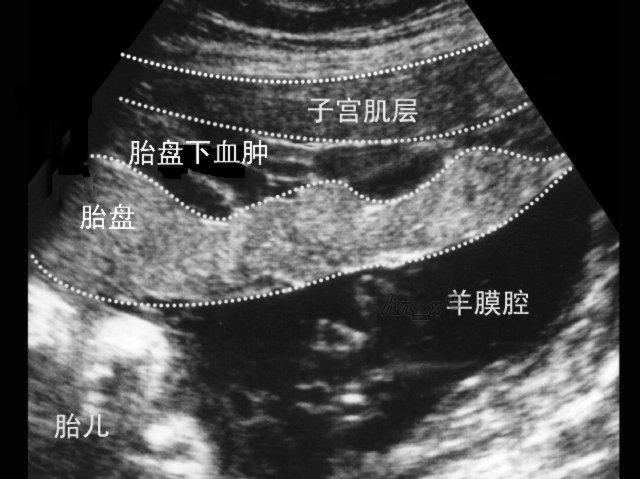

胎盘是胎儿的附属物,如同树根植入大地吸取营养,胎盘吸附于母体子宫体壁上,其重要功能就是母体与胎儿进行氧气、二氧化碳交换,也是胎儿吸收营养物质和排泄代谢产物的渠道。胎盘将母体血液中的葡萄糖,氨基酸,脂肪酸分别合成糖原,蛋白质,脂肪后供给胎儿利用;将胎儿的代谢废物:乳酸、尿素、尿酸、肌酸等传送给母血,经母体代谢排出体外。胎盘的规矩就是“瓜熟蒂落”,在胎儿成熟娩出子宫后,胎盘后续剥离排出子宫。但是,如果胎盘不守规矩,在胎儿娩出子宫前发生剥离,就是所谓的胎盘早剥。

胎盘一旦剥离,胎儿意味着氧气和能量物质的供应终止,此时,如果不能迅速娩出胎儿,轻则胎儿窘迫,神经受损,甚至胎死宫内;重则胎盘剥离面的出血导致母亲子宫卒中,凝血功能障碍,肾功能不全,弥散性血管内凝血(DIC),进而多脏器功能衰竭死亡。胎盘早剥的母儿预后与胎盘早剥的面积和进展,以及是否有妊娠期高血压疾病有关,还与是否及时取出胎儿有密切关系。

在清明小长假期间,解放军 306 医院妇产科就发生了一起胎盘早剥紧急剖宫产。值班一线医生陈瑾和二线医生鲁泽春刚顺利完成一例羊水三度合并高度近视,行试管婴儿的高龄孕妇的剖宫产手术,正进行着晚间查房。待产室电话呼叫:宫口开大 3 厘米,刚待产的孕妇胎心监护显示胎心下降明显。陈瑾医生终止查房到待产室查看情况,当她看到孕妇的胎心监护曲线一度下降到 90 次,立即电话通知正在查房的鲁泽春医生速到产房,二线鲁泽春医生到产房后,迅速查看患者后,当机立断:患者胎心突然下降明显且不能恢复,不排除胎儿窘迫,胎盘早剥,急诊就地剖宫产;陈瑾医生交待病情家属签字,助产士备皮,护士站通知手术麻醉室、儿科医师紧急抢救。立即开始洗手,消毒,铺无菌单,穿手术衣,快速清点手术器械,安装手术刀片,抽取利多卡因局部麻醉,待助手陈瑾医生签字完毕穿好手术衣后,切开皮肤及皮下组织,撕开皮下脂肪,剪开筋膜,分离腹直肌,剪开腹膜,暴露子宫下段。此时手术麻醉室医生护士,儿科医生已经到场就位,继续加强麻醉,划开子宫壁,止血钳撑开子宫下段,吸净喷涌而出的羊水,伸手取头,加压,胎头娩出,抬后肩,压前肩,捋净新生儿口鼻羊水,新生儿一生啼哭响起,断脐带交台下处理。成功了!6 分钟,发现异常到就地剖宫产胎儿取出。后续的手术按部就班进行,宫体注射缩宫素、欣母沛,娩出胎盘,天哪,胎盘已经近 1/2 已经发生了早剥。钳夹子宫下段切缘止血,胎盘娩出后宫缩差,宫腔出血较多,继续按摩宫体促进子宫复旧,分层缝合子宫下段、腹膜、皮下组织,可吸收线皮内美容缝合皮肤切口。一切就在电光火石、兔起鹘落之间,而这短短一瞬间,决定着一个新生儿的生命,一位母亲的期盼,一个家庭的幸福!

胎盘早剥是产科急症,其发生原因主要与母亲全身情况,以及子宫局部状态相关,全身情况有:孕妇并发妊娠期高血压疾病或肾脏疾病,因小动脉痉挛或硬化导致胎盘自子宫壁剥离,孕妇年龄大与产次增多胎盘早剥发生也增多,也有报道吸烟产生的尼古丁,滥用可卡因导致血管脆性增加导致胎盘早剥增多。子宫局部因素有:子宫受到外力撞击,胎膜早破羊水快速流出,双胎妊娠一胎娩出后造成胎盘子宫相对错位引起早剥,还有妊娠晚期子宫压迫腹腔静脉,引起静脉压升高导致胎盘蜕膜静脉床淤血造成早剥。而本例胎盘早剥没有任何诱因,产科的高风险可能在于此吧。对于胎盘早剥的预防,孕妇做好定期产检,积极治疗妊娠期高血压,避免外伤撞击,对于医疗机构来说,加强规范制度建设以及人员培训,早期识别和救治胎盘早剥。